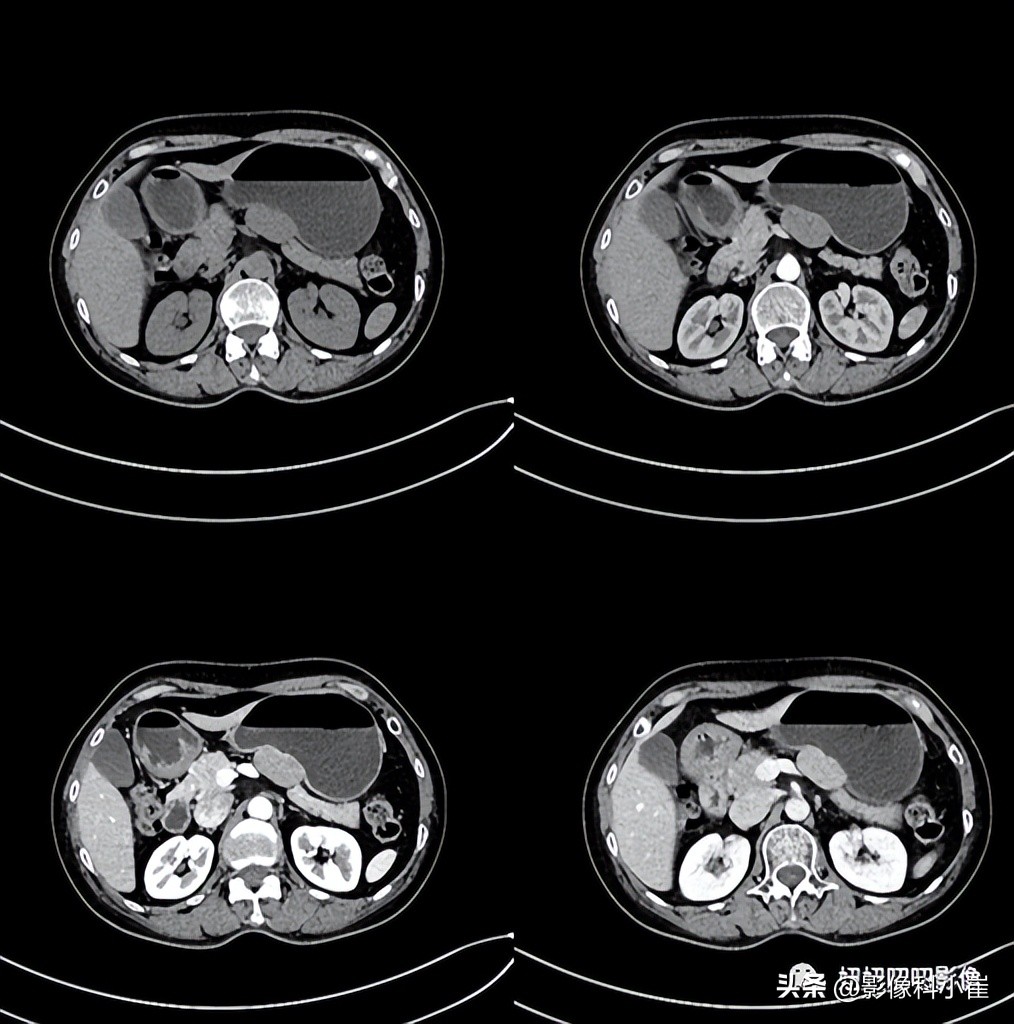

图像:

胃充盈尚可,后壁见一类椭圆形软组织密度灶,大部分外突,密度尚均匀,截面约3.7X2.3cm,增强扫描明显均匀强化,胃窦及幽门壁略增厚,管腔略窄,增强扫描明显强化。